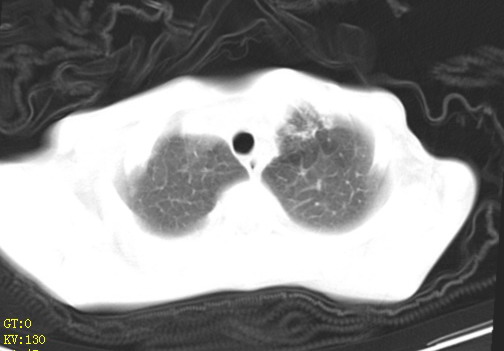

女,12岁,气促、咳嗽2天,3个月前查胸片示:两肺感染,急诊入院查ct,血常规等未检查。

左肺上叶改变考虑继发性肺结核,余双肺重症肺炎不排除h1n1。双侧胸腔少量积液。

双肺中下野不规则片絮状阴影,中外带明显,双侧胸腔少量积液,心影增大,心腔密度减低,隆突下及左侧气管旁见钙化淋巴结影,考虑双肺感染、心衰;建议结合临床除外h1n1并急性心衰,先心不能排除。

两肺多发片絮状模糊影,以下肺外带居多,内见支气管气像,纵膈窗未减影,两侧胸腔积液,心影增大,结合心超,支持重症肺炎,非常时期,甲型h1n1流感不排除。